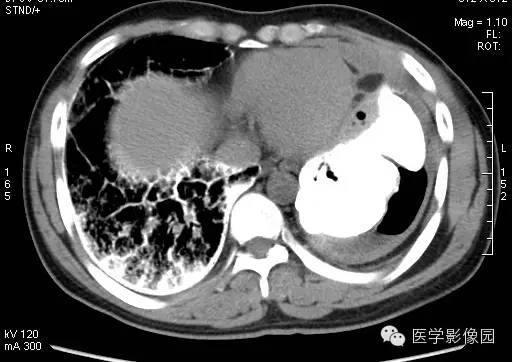

【病例】尘肺1例X线及CT影像表现

男性,36岁,镀锌工作史1年。

小结节影:多为双肺弥漫性或散在小结节影,表现为类圆形影,边界清晰,以中下肺为主,背侧多见。

大阴影:多为块状大阴影,表现为不规则卵圆形影,边缘凹凸不平,多有粗大索条影,伴疤痕性肺气肿,其内可见点状、斑片状钙化,坏死或空洞。

尘肺的主要病理改变为肺间质弥漫性纤维化及弥漫性灶周肺气肿,主要累及周围肺组织和支架结构,如肺泡壁、小叶间隔和支气管血管周围组织。